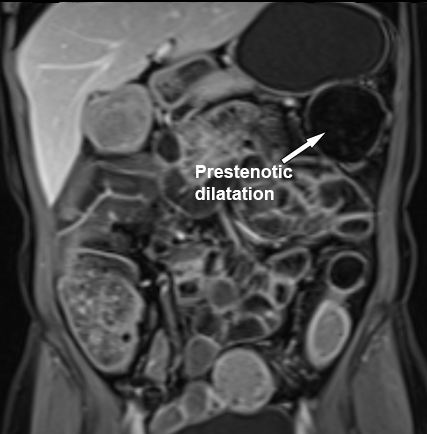

Sự hiện diện của giãn ruột trước chỗ hẹp làm tăng khả năng chẩn đoán hẹp lòng ruột.

Trong hệ thống phân độ, chỉ hẹp nặng mới được xếp vào nhóm biến chứng, được định nghĩa là hẹp có giãn ruột trước chỗ hẹp và tín hiệu T2W thành ruột tăng mức độ vừa đến rõ rệt.

Phát hiện hẹp lòng ruột ở đại tràng sigma, không thể vượt qua được khi nội soi.

MR-enterography được thực hiện để đánh giá mức độ lan rộng của chỗ hẹp.

Ruột non bình thường, nhưng ghi nhận các đoạn hẹp ở đại tràng xuống và đại tràng ngang.

Cả hai đoạn hẹp đều có thành ruột dày đến 8 mm và ngấm thuốc rõ rệt theo kiểu niêm mạc ở đại tràng xuống và kiểu phân lớp ở đại tràng ngang.

Giãn ruột trước chỗ hẹp được ghi nhận ở cả hai đoạn.

Do các chỗ hẹp này không hiện diện khi nội soi đại tràng trước khi điều trị kháng TNF, nhiều khả năng chúng đã hình thành trong quá trình điều trị.

Do đó, quyết định phẫu thuật cắt đại tràng gần toàn bộ với miệng nối hồi-sigma đã được đưa ra.